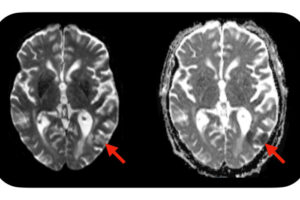

An idea that has propelled Alzheimer’s research for more than 30 years is approaching its day of reckoning. Scientists are launching a study designed to make or break the hypothesis that Alzheimer’s is caused by a sticky substance called beta-amyloid. The study will give an experimental anti-amyloid drug to people as young as 18 who […]